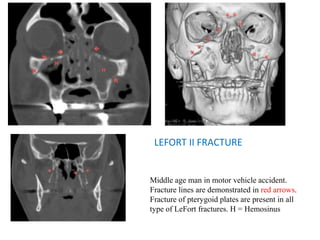

LEFORT II FRACTURES

• Pyramid-shaped maxillary fracture, involving maxillary

sinuses (anterior-lateral walls), inferior orbital rim,

orbital floor and nasofrontal suture.

• Clinical: free floating, movable midface including

maxillary teeth, hard palate and nose.

• Imaging findings:

Opacified bilateral maxillary sinuses and orbital

emphysema

Fractures of anterior/lateral walls of maxillary

sinuses, inferior orbital rims/floors and disruption

of nasofrontal suture

Best seen and confirmed by coronal reformatted

CT images

LEFORT II FRACTURE

Middle age man in motor vehicle accident.

Fracture lines are demonstrated in red arrows.

Fracture of pterygoid plates are present in all

type of LeFort fractures. H = Hemosinus